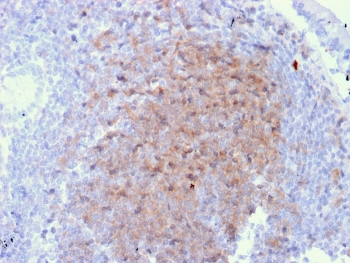

IHC staining of FFPE human lymph node with CD72 antibody (clone BU40). HIER: boil tissue sections in pH9 10mM Tris with 1mM EDTA for 20 min and allow to cool before testing.

IHC staining of FFPE human lymph node with CD72 antibody (clone BU40). HIER: boil tissue sections in pH9 10mM Tris with 1mM EDTA for 20 min and allow to cool before testing.